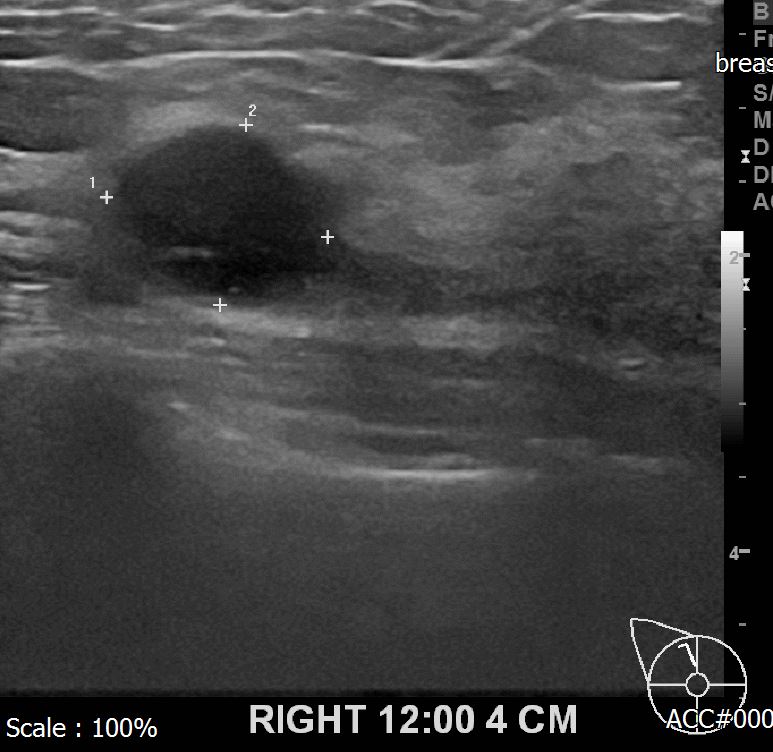

상기환자 외부검사상 이상소견으로 내원하셔셔 경과관찰중인 56세 여성분으로

초음파 검사후 새로이 확인되는 우측의 의심스런혹이 있어 조직검사 시행해

유방암 진단되었읍니다